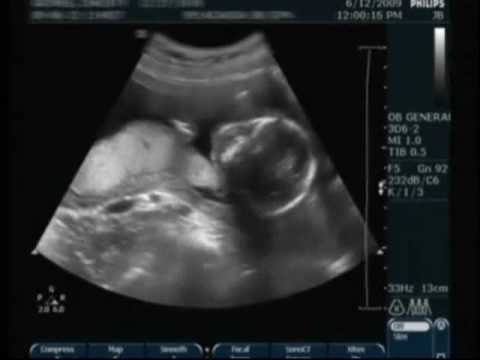

An ultrasound / SONOGRAPHY is a procedure that uses high-frequency sound waves to scan a the internal organs of the body woman’s abdomen and pelvic cavity, the reproductive system and the fetus of a pregnant woman creating a picture (sonogram) of the baby and placenta. Although the terms ultrasound and sonogram are technically different, they are used interchangeably and reference the same exam. They can show the structure and movement of the body's internal organs, including the abdomen, the fetus of pregnant women as well as blood flowing through blood vessels

An ultrasound / SONOGRAPHY is a procedure that uses high-frequency sound waves to scan a the internal organs of the body woman’s abdomen and pelvic cavity, the reproductive system and the fetus of a pregnant woman creating a picture (sonogram) of the baby and placenta. Although the terms ultrasound and sonogram are technically different, they are used interchangeably and reference the same exam. They can show the structure and movement of the body's internal organs, including the abdomen, the fetus of pregnant women as well as blood flowing through blood vessels.

Ultrasound imaging also called as sonography uses a transducer or probe to generate sound waves and produce pictures of the body's internal structures. It is often used to help diagnose unexplained pain, swelling or infection. It is used to see internal body structures such as tendons, muscles, joints, vessels and internal organs. It may also be used to provide imaging guidance to needle biopsies or to see and evaluate conditions related to blood flow. It is also the preferred imaging method for monitoring a pregnant woman and her unborn child. It does not use ionizing radiation, has no known harmful effects, and provides a clear picture of soft tissues that don't show up well on x-ray images.Most of these level II ultrasounds should be done in the second trimester of pregnancy usually between 18 and 22 weeks. It uses sound waves to produce pictures of a baby (embryo or fetus) within a pregnant woman, as well as the mother's uterus and ovaries. It does not use ionizing radiation, has no known harmful effects, and is the preferred method for monitoring pregnant women and their unborn babies. A Doppler ultrasound study – a technique that evaluates blood flow in the umbilical cord, fetus or placenta – may be part of this exam. It is a totally painless and safe procedure. It is useful test to establish the presence of fetus, estimate the age of pregnancy, diagnose congenital abnormalities of the fetus, assess fetal growth and well being etc. Preparation - No special preparation is needed.